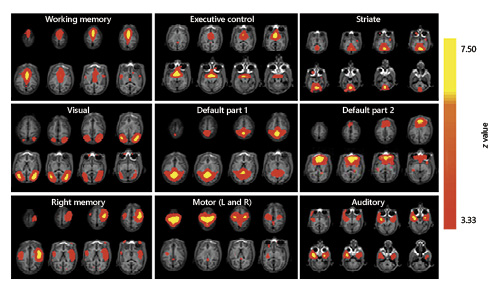

The group-level ICA yielded nine networks of interest, identified through spatial cross-correlation and with reference to the previous literature in healthy human brains [Damoiseaux et al., 2006]. The networks are named on the basis of their close correspondence with task-based networks: 2 executive function networks (WM and EC); striate network, visual network; 2 default-mode networks, 1 memory network (right), 1 motor network; and 1 auditory network [Damoiseaux et al., 2006] (Fig. 1). Various components were projected onto T1 axial of the first subject (Fig. 1).

Resting-state networks in the spider monkey. Networks are presented overlaid on axial slices of a monkey’s brain. The networks shown are executive control, working memory, visual, ventral salience, dorsal salience, right memory, audition, default parts 1 and 2, extrastriate, and motor (left and right). The pseudocolored scale indicates levels of statistical significance.

The main difference in the resting-state networks obtained was that the executive networks of the monkeys (EC and WM) were separated into two components and merged for the human group. Although memory networks are not addressed in this study, it is important to point out that another difference found was that Ateles only has one memory network, while the human group has two memory networks (Fig. 1, 2 and online suppl. Table S1; see www.karger.com/doi/10.1159/000499177 for all online suppl. material).